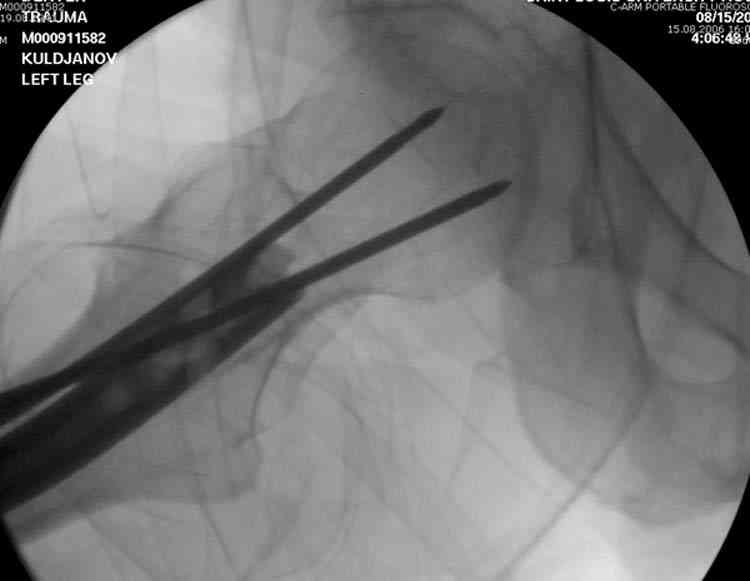

Здесь представлены снимки больного 65 лет, поступившего с диагнозом перелом

бедра после автоаварии.

В первый же день произведено антеградное штифтованием DePuy Trochanteric Nail.

На второй день (7) обнаружен пропущенный перелом,

сделаны Компьютерная Томограмма

и проведены шурурпы через и спереди штифта без удаления.